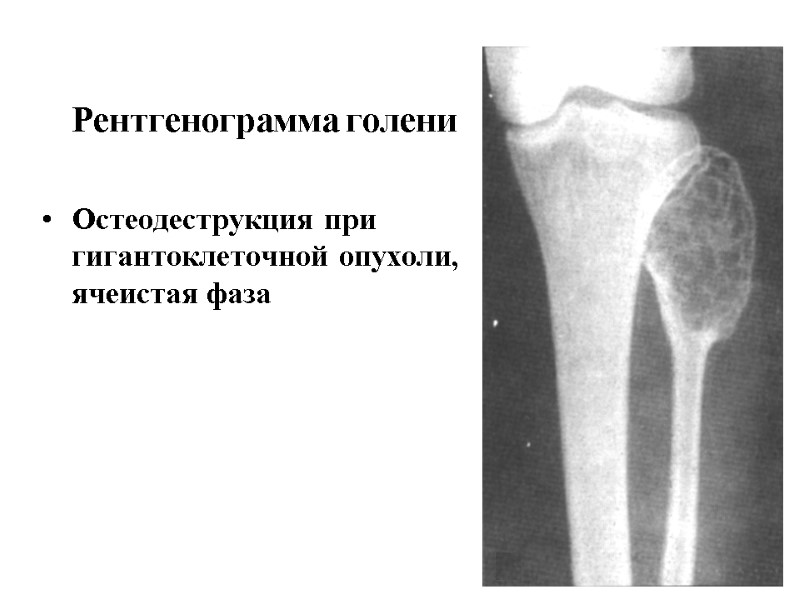

Рентгенограмма голени Остеодеструкция при гигантоклеточной опухоли, ячеистая фаза